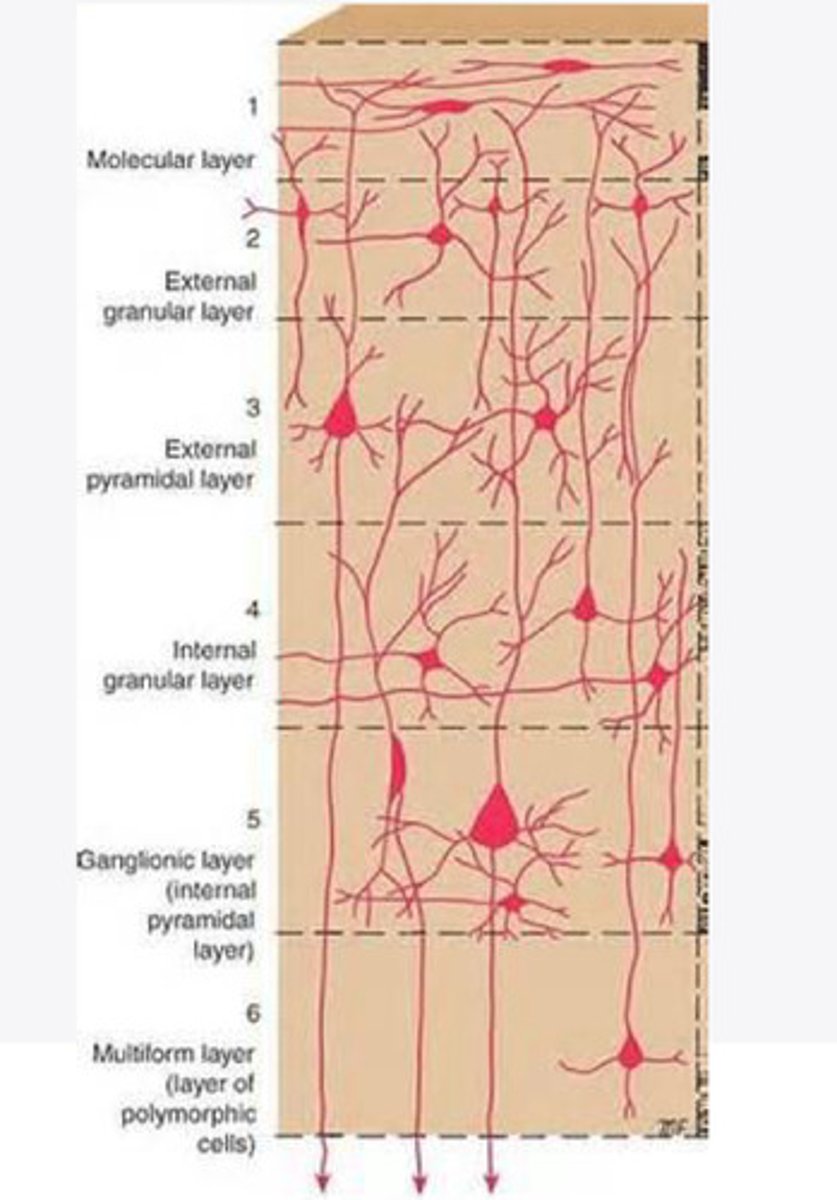

divided into 6 distinct layers, due to varying densities of cell body types within each layer

The cortex of the brain is divided into how many layers? Why is it divided into layers?

Layers of the cortex of the brain pic

2 and 4

What are the layers of the cortex that are associated with input?

3 and 5

What are the layers of the cortex that are associated with output?

molecular layer

What is the name of Layer 1 of the cortex of the brain?

very few cells

Does Layer 1 of the cortex have a lot or few cells?

receives dendrites from internal layers so it may actually function as a coordinating center where layers can communicate action

What does Layer 1 of the cortex do?

1

Every layer sends densities to Layer ____?

1

What layer serves as the "water cooler" of the brain?

external granular layer

What is the name for layer 2 of the cortex of the brain?

receives input from other cortical regions

What is the function of Layer 2 of the Cortex of the brain?

Stellate

What type of cells (stellate/pyramidal) would be most concentrated in Layer 2?

external pyramidal layer

What is the name for layer 3 of the cortex of the brain?

sends output to the other cortical layers

What is the function of Layer 3 of the cortex of the brain?

pyramidal

What type of cells (stellate/pyramidal) would be most concentrated in Layer 3 of the brain?

Layers 2 and 3

What layers are associated with association and commissural fibers?

Layer 3 - axons of cell bodies

Layer 2 - synapse into target areas in Layer 2

What part of the axons is in Layer 2/ in layer 3?

Layer 3 - external pyramidal layer

All axonal cel bodies for association and commissural fibers lie within what layer of the Cortex of the brain?

internal granular

** or called the striate cortex because it is so thick that you can see a line through this layer even in unstrained brain slides

What is the name for the 4th layer of the cortex of the brain?

receives input from the thalamus, geniculocortical layer, and other brainstem areas

What is the function for the 4th layer of the Cortex of the brain?

very thick within the vision, auditory, and somatosensory areas

Is Layer 4 thick or thin within SENSORY areas of the cortex?

Internal pyramidal

What is the name for Layer 5 of the cortex of the brain?

sends axons to the brainstem (corticobulbar) and spinal cord (corticospinal)

What is the function of Layer 5 of the cortex of the brain?

in motor areas of the cortex?

Where is layer 5 very thick in the brain?

the frontal lobe -- very motor heavy

What lobe of the brain will have a thick layer 5 of the cortex of the brain?

the multiform layer

What is the name of layer 6 of the cortex of the brain?

-sends axons back to the thalamus through corticogeniculate fibers

-modulates what information the thalamus sends to the cortex to control the strength of the signal received and modulate what you pay attention to

What is the function of layer 6 of the cortex of the brain?

no

Is layer 6 a motor layer?